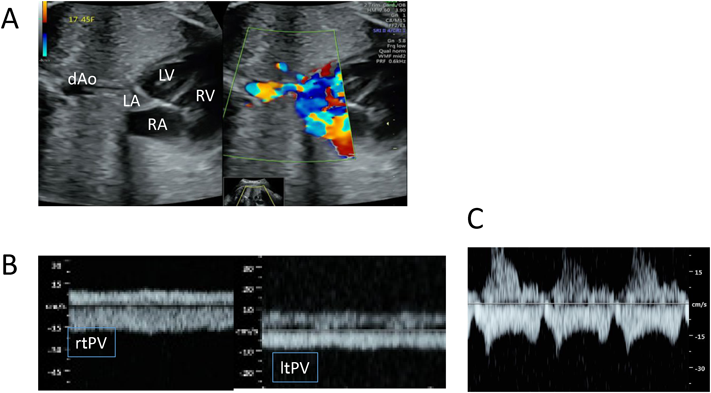

大きなVSDおよび左室流出路の観察で大動脈騎乗と太い大動脈を認める.右室流出路狭窄の程度は,肺動脈閉鎖(pulmonary atresia: PA)を合併したいわゆる「極型TOF(心室中隔欠損を伴う肺動脈閉鎖)」から肺動脈弁下にごく軽度の狭窄のみの「pink TOF」まで様々であり重症度が異なる.典型的な肺動脈狭窄(pulmonary stenosis: PS)合併の場合は,その程度の評価が重要である.動脈管血流の逆行(大動脈から肺動脈方向)があれば出生後に動脈管(patent ductus arteriosus: PDA)依存肺血流となることが予想される(Fig. 2).PA合併の場合は,肺血流がPDA依存か主要大動脈肺動脈側副血行路(major aortopulmonary collateral artery: MAPCA)依存なのか確認し,PDA依存ならその位置と太さを,MAPCA合併ならその位置と中心肺動脈(central pulmonary artery)の有無と太さの確認が重要である.また稀だが重症なTOFとして肺動脈弁欠損合併がある.これは,肺動脈弁尖が欠損して弁輪のみ遺残しており,著しい肺動脈弁閉鎖不全により肺動脈が巨大な瘤状に形成される(Fig. 3(video)).そのため胎児期に見つかりやすいが胎児死亡例も多く,出生後も重度心不全や呼吸不全を来すため胎児期より肺動脈形態や肺動脈狭窄・閉鎖不全の評価をして予後の推定をすることが重要である5).またTOFでは30~40%に染色体異常や奇形症候群,中でも21trisomyや22q11.2欠失症候群を合併することが多いので胸腺の確認や心外奇形(肺や腹部など)の有無の確認も重要である.

Ebstein病は重症度に幅のある疾患であるが,胎児期に診断されるものは心拡大を伴う重症例が多い.Ebstein病を診断した際には,肺動脈狭窄・閉鎖を合併しているかどうか,肺動脈閉鎖であれば機能的閉鎖(functionalPA)か解剖学的閉鎖(anatomicalPA)かどうかを確認して治療方針を決定する.重症度の評価としては右房と右房化右室を計測するCelermajer Scaleやそれを利用したSASscoreがある13, 14).また三尖弁逆流の最大流速も参考になる15).肺動脈弁逆流を多く認める場合にはcircular shuntを呈する最重症のEbstein病として胎児死亡もしくは出生後も治療に難渋することが多い16).具体的には,重度三尖弁逆流によりうっ滞した右房の血流(Fig. 5A(video))が卵円孔を介して左房,左室,上行大動脈,そして動脈管を逆行し(Fig. 5B(video)),さらに主肺動脈から右室へ逆流する(Fig. 5C(video))circular shuntとなり胎児心不全となる状態である.